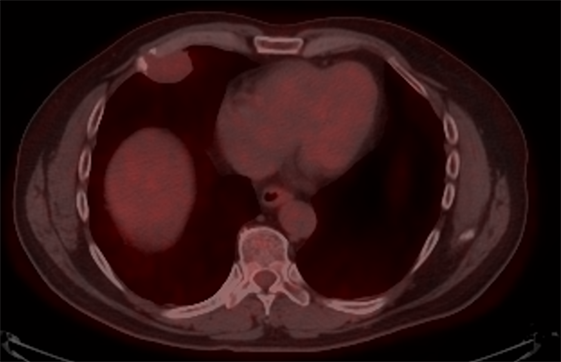

A 60-year-old Hispanic male presented to his primary care physician office with an asymptomatic, but palpable right anterior chest wall mass. The patient has no significant past medical history except for a clavicular fracture sustained during soccer. Physical examination revealed an asymptomatic 4 cm soft tissue palpable mass of the right anterior chest wall. The skin was intact, no erosive markings were present. The patient’s laboratory work up was unremarkable. Radiology work up included CT chest, MRI of the chest and PET/CT. His CT chest axial series on bone windows demonstrated a 2.8 × 3.8 × 2.9 cm pleural based soft tissue mass eroding through the right anterior fifth rib (Figure 1). There was mild compression of the nearby lung parenchyma, however no pulmonary lesions were identified. Further characterization of the mass by MRI contrast enhanced images of the chest revealed a well-circumscribed pleural based T1 hypo-intense avidly enhancing soft tissue mass in the right anterior chest wall involving the right anterior fifth rib and into the overlying sub-pectoral soft tissues (Figure 2). The mass also demonstrated restricted diffusion which is indicative of high cellularity (Figure 3 and Figure 4). PET/CT imaging revealed mild hypermetabolic activity of the mass with maximum SUV of 1.9 (Figure 5).

Figure 5. Axial fused PET/CT image at the level of the lower chest shows a soft tissue mass with osseous destruction of the anterior fifth rib with a maximum standard uptake value (SUV) of 1.9.

Positron emission tomography combined with computed tomography (PET/CT) provides a functional information of the tumor with analysis of active glucose consumption. The higher the metabolic activity the higher the glucose consumption and hence the PET/CT signal. In general, malignant cells have higher metabolic rate relative to the normal soft tissue background. The active lesions will display a high signal which is indicative of active disease.